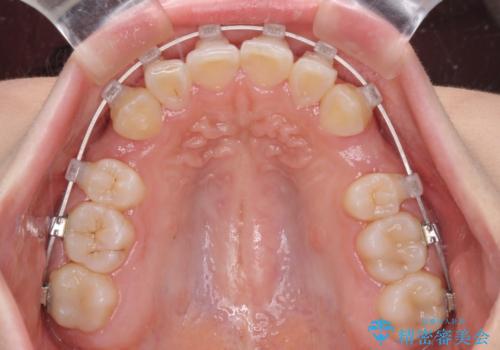

- クリアブラケット

- 上顎の八重歯と、上下前歯のデコボコを気にして来院された患者様です。

奥歯の咬み合わせを見ると、上顎臼歯が下顎に対して前方にあり、叢生改善により口元が突出する顔貌ではなかったため、上顎左右第一小臼歯2本を抜歯し、ワイヤー装置にて矯正治療を行うこととしました。

前歯部のデコボコがなくなったため、歯磨きしやすくなり、非常に清潔な状態になりました。